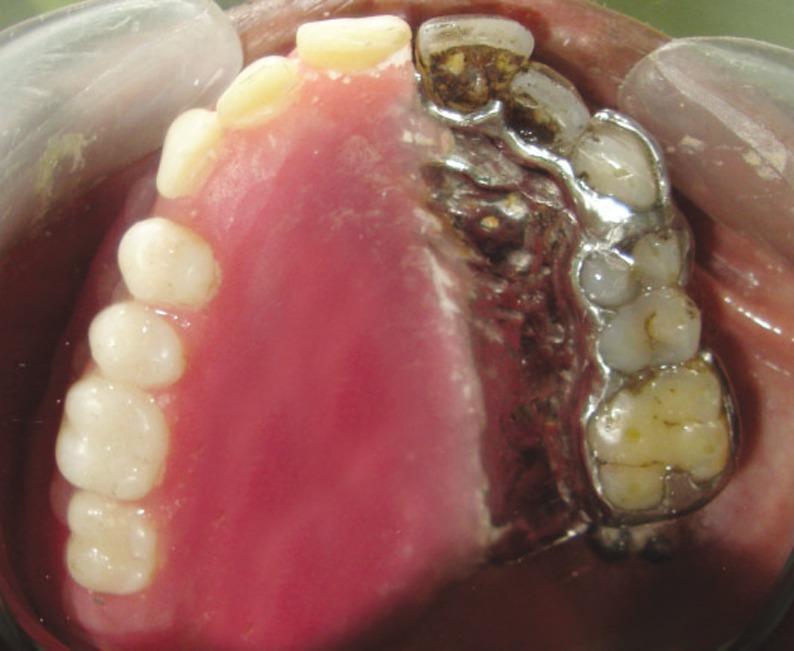

Facial prosthesis is generally considered over surgical reconstruction to restore function and appearance in patients with facial defects that resulted from cancer resection. Retention of the prosthesis is challenging due to its size and weight. Retention can be achieved by using medical grade adhesives, resilient attachments, clips and osseointegrated implants. It can also be connected to obturator by magnets. This clinical report highlights the rehabilitation of a lateral midfacial defect with a two piece prosthesis that included an extra oral facial prosthesis and an intraoral obturator with the use of magnets.

面部假体通常被认为优于手术重建,可用于因癌症切除而导致面部缺陷的患者,以恢复功能和外观。由于假体的大小和重量,保留假体具有挑战性。可以使用医用级粘合剂、弹性附件、夹子和骨整合植入物来实现保留。也可以通过磁铁将其连接到闭塞器上。本临床报告重点介绍了使用磁铁通过两部分假体(包括口腔外面部假体和口腔内闭塞器)来修复侧面部中部缺损的康复情况。